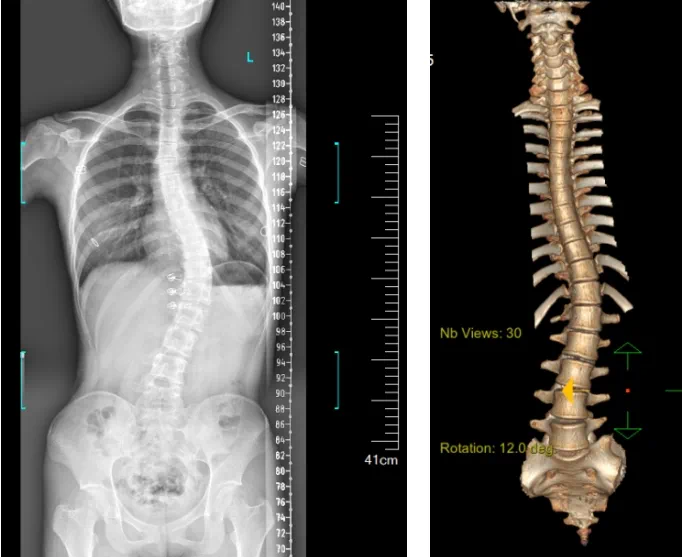

患者为一名16岁女孩,,,,,发明脊柱侧弯1年,,,,,到南方医院赣州医院脊柱外科求诊。。。。。经查体,,,,,患者左右胸廓差池称,,,,,双肩等高,,,,,左肩胛骨隆起,,,,,背侧呈“剃刀背”畸形,,,,,胸腰段棘突偏离正中线,,,,,胸腰段脊柱左侧凸畸形;;;;;;各棘突无压痛及叩击痛,,,,,右侧腰部凹陷,,,,,胸腹及腰背部感受正常。。。。。检查发明患者特发性脊柱侧弯,,,,,Lenke5C型,,,,,主胸弯51°。。。。。唬唬唬唬唬患者及眷属对外观不知足,,,,,为改善外观及功效,,,,,要求手术矫形治疗。。。。。

据悉脊柱侧弯手术治疗后可以坚持躯干平衡,,,,,改善外观并避免畸形进一步生长。。。。。唬唬唬唬唬患者的生涯质量获得提高,,,,,进而镌汰脊柱太过畸形可能带来的疾病的爆发率,,,,,外观上的起劲转变往往也能带来患者心理与精神的起劲转变。。。。。临床上会综合思量患者的年岁、侧弯水平、希望趋势、骨质条件、相近节段情形、手术节段等因素,,,,,合理接纳个性化的手术方法举行治疗。。。。。然而,,,,,由于脊柱神经血管密布,,,,,手术操作相对重大,,,,,手术难度高、危害大,,,,,古板脊柱侧弯的手术方法往往有较高的神经或脊髓损伤危害。。。。。故此次科室决议开展机械人辅助导航下脊柱侧弯矫形、植骨融合内牢靠手术。。。。。术前,,,,,医生团队在机械人多维度图像融合智能手术妄想功效的辅助下,,,,,预先妄想了理想的置钉路径。。。。。术中,,,,,天玑骨科手术机械人准确遵照术前妄想,,,,,凭证配准效果,,,,,实时定位并准确执行置钉操作,,,,,所有导针均用电钻置入,,,,,一次性乐成,,,,,协助医生顺遂完成手术。。。。。最终,,,,,在麻醉科、手术室亲近配合下,,,,,历时3小时乐成完成侧弯矫形术,,,,,出血量仅500ml。。。。。术后,,,,,患者恢复优异,,,,,巨细便及下肢神经运动感受正常。。。。。

图为置钉后